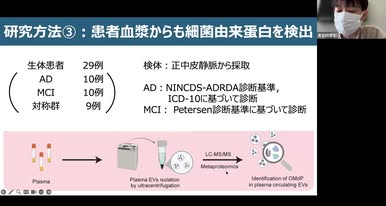

・岐阜大学脳内抄読会 第104回 「口腔内細菌由来タンパクは認知症における有用なバイオマーカーとなり得るか」

***岐阜大学医学部下畑先生の2026年3月26日のFB投稿です***

今週のオンライン抄読会です.今回は医学部4年生の東吉行君の担当で,2025年にMol Cell Proteomics誌に発表された,口腔内細菌と認知症の分子機序に迫る興味深い論文でした.大変完成度の高い発表で,参加者一同,関心しながら拝聴しました.

今週のオンライン抄読会です.今回は医学部4年生の東吉行君の担当で,2025年にMol Cell Proteomics誌に発表された,口腔内細菌と認知症の分子機序に迫る興味深い論文でした.大変完成度の高い発表で,参加者一同,関心しながら拝聴しました.

口腔内環境と認知症の関連は疫学的に知られていますが,本研究はそのメカニズムに踏み込んだ点が特徴です.死後脳から分離した細胞外小胞(EV)を網羅的に解析し,口腔内細菌由来タンパク質が実際に脳内に存在することを示しています.さらに,これらのタンパクはアルツハイマー病の進行段階に応じて変動し,アミロイドやタウとの相互作用も示唆されました.

加えて,血中EVにも同様のタンパクが検出され,in vitroモデルでは細菌由来EVが血液脳関門を通過する可能性も示されています.すなわち,「口腔内細菌→EV→脳」という新たな病態連関の経路が提示された点は,インパクトの大きい知見です.

発表は16分,質疑は18分でした.私も木村先生も容赦なく議論させていただきましたが,それに対する応答も含め,大変立派な内容でした.